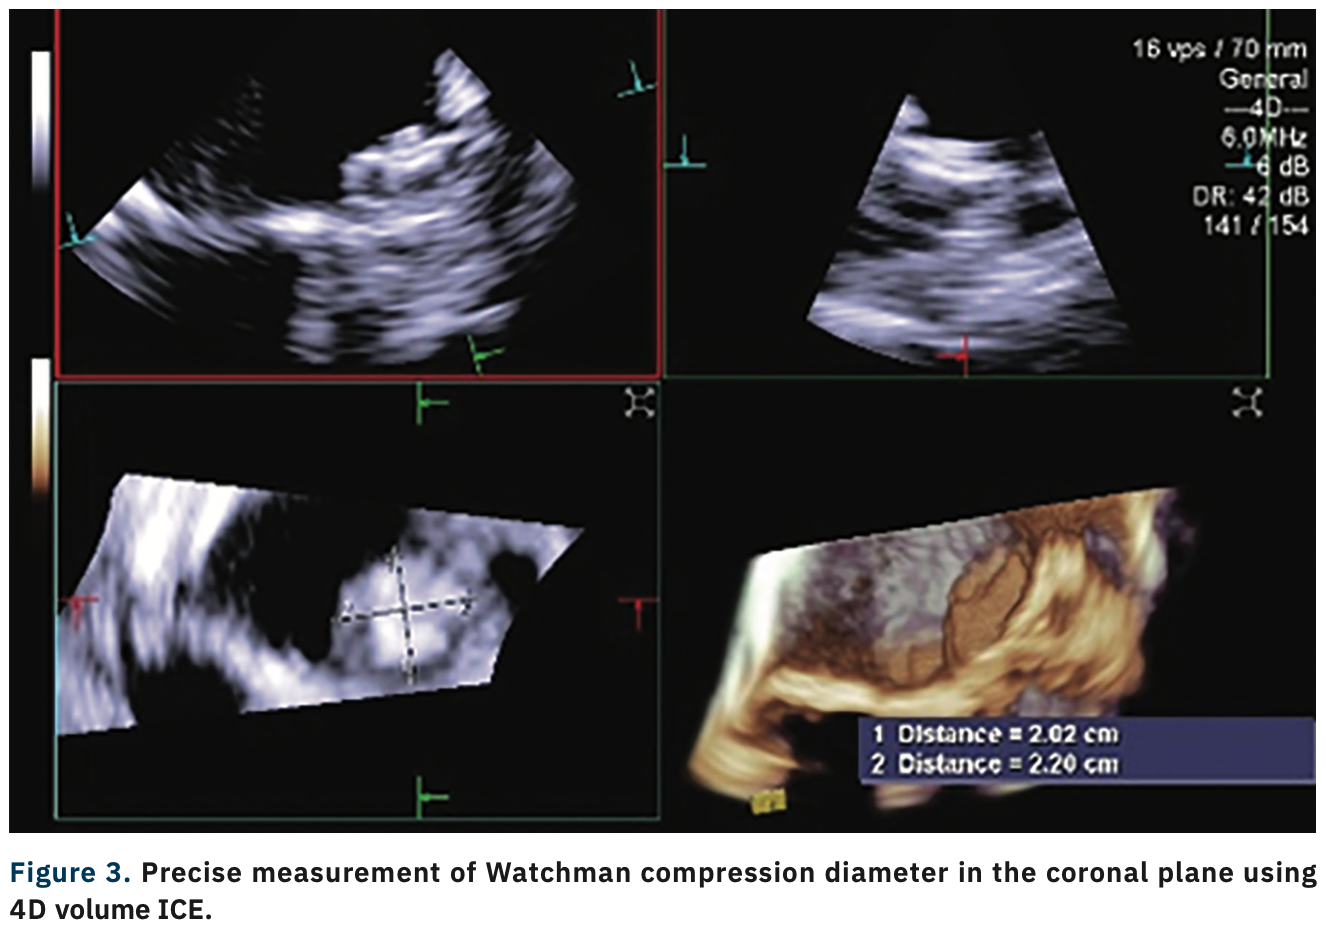

This case of left atrial appendage closure (LAAC) with a Watchman device (Boston Scientific) demonstrates the advantages of using 4D intracardiac echocardiography (ICE) over transesophageal echocardiography (TEE) and 2D ICE. An 87-year-old female with a history of paroxysmal atrial fibrillation was referred for LAAC. She received a contrast-enhanced preprocedural computed tomography (CT) scan to evaluate the LAA’s dimensions and anatomy. 4D ICE measurements (18.9 mm) of the LAA ostium correlated well with CT (18.2 mm). Since the patient could not tolerate long-term anticoagulation medication due to her condition, she underwent a Watchman procedure. Precise measurement of the landing zone predeployment and PASS (Position- Anchor-Size-Seal) criteria was performed using 4D ICE (ACUSON SC2000 PRIME ultrasound system, Siemens Healthineers). The Watchman device was deployed with the 4D ICE catheter positioned in the mid left atrial view displaying multiplanar reconstruction imaging, rather than with multiple views using 2D ICE. Device implantation occurred under conscious sedation and was free from complications; the patient was discharged the same day.